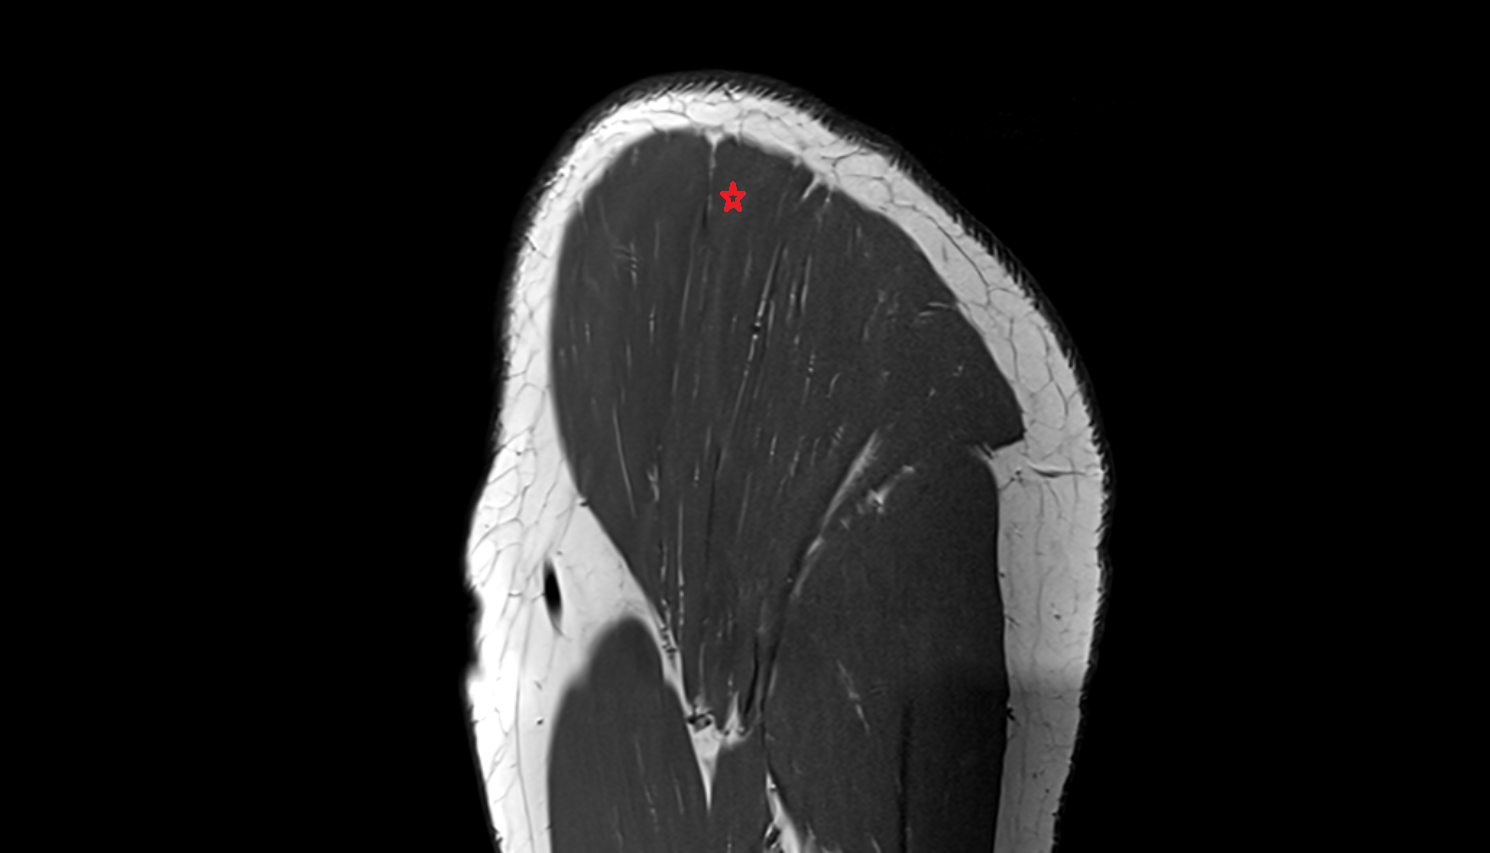

- Supraspinatus tendon